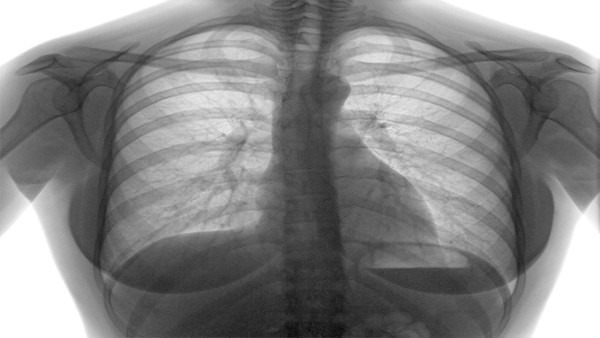

呼吸困难是病情加重的关键信号

当病毒侵袭至下呼吸道时,患者会着手感觉到胸闷以及气短。在正常情形下,成年人静息呼吸频率乃是每分钟16至20次,要是显著增快,或者略微活动便喘不过气来的话,表明肺部或许已然遭受较大影响。在这个时候,血氧饱和度也会降低,低于93%就需予以高度警惕。

发病后的一周左右,常常会出现呼吸困难的情况。有一位来自武汉的康复患者叙述称,那几日感觉自己好似被什么物件给压住了胸口,想要大口吸气然而却十分费劲。在这个阶段不可以再在家里进行观察了,务必要尽快联系医院或者寻求急救,缘故是病情有可能在短时间之内快速恶化。

严重症状直指多器官危机

一部分患者会快速演化为急性呼吸窘迫综合征,这意味着肺内充斥着炎性渗出物,致使气体交换遭遇阻碍,仅仅依靠鼻子吸氧已然不足够了,需要借助有创呼吸机乃至ECMO(人工肺)来维系生命。数据表明,在重症患者当中约有15%至20%会发展至这个阶段。